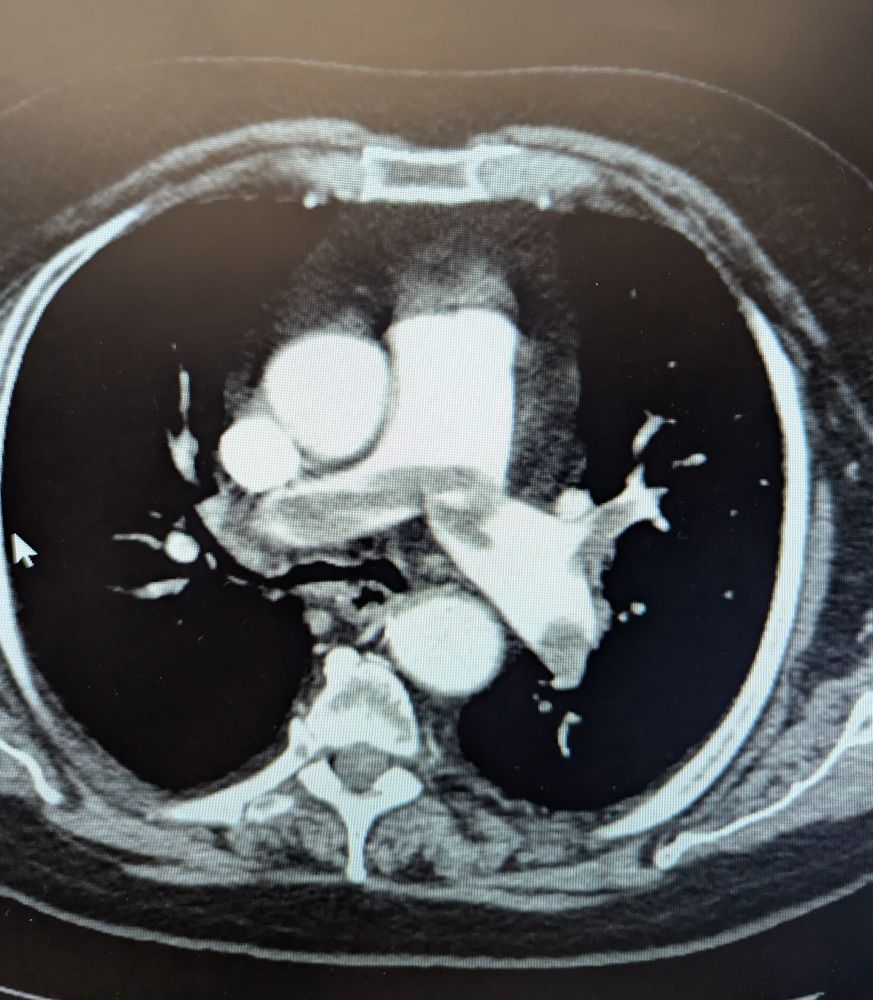

What would you treat this saddle embolism going into both right and left pulmonary arteries?

Systemic tpa? Intra arterial tpa? Interventional radiology? Ct surg for embolectomy?

#medsky #emedsky #radsky